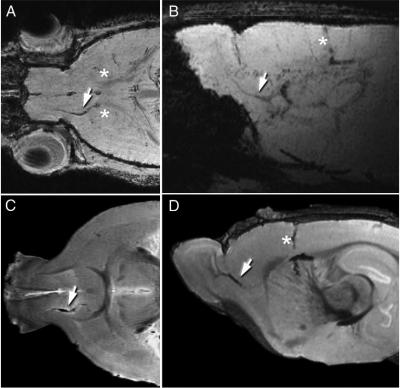

In the current study, Iordanova and Ahrens used the same technique as in the initial study, this time tagging neuroblasts with the engineered ferritin. They incorporated the DNA sequence for the engineered metalloprotein into an adenovirus vector, which they then injected into the subventricular zone of a rat brain. The adenovirus infected the neural stem cells giving the cells the genetic instructions to begin producing the ferritin reporter. Iordanova then imaged the brain with MRI and found that she was able to follow — in real time — the neuroblasts as they traveled toward the olfactory bulb and ultimately formed new inhibitory neurons. These results mirrored what had been observed in histology studies.